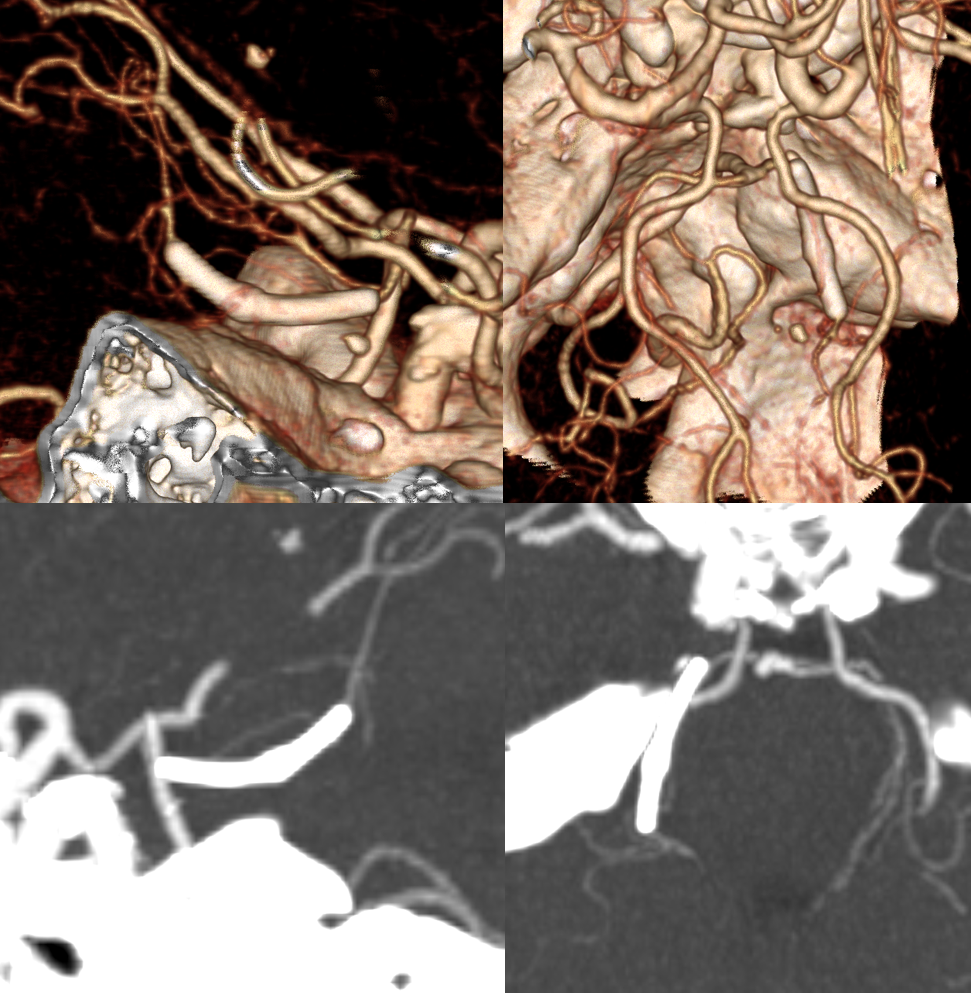

Vantage treatment of a ruptured SCA Vermian Division Pseudoaneurysm

Follow up 3 mo CTA — excellent clinical recovery. Age too advanced for angio given excellent CTA results